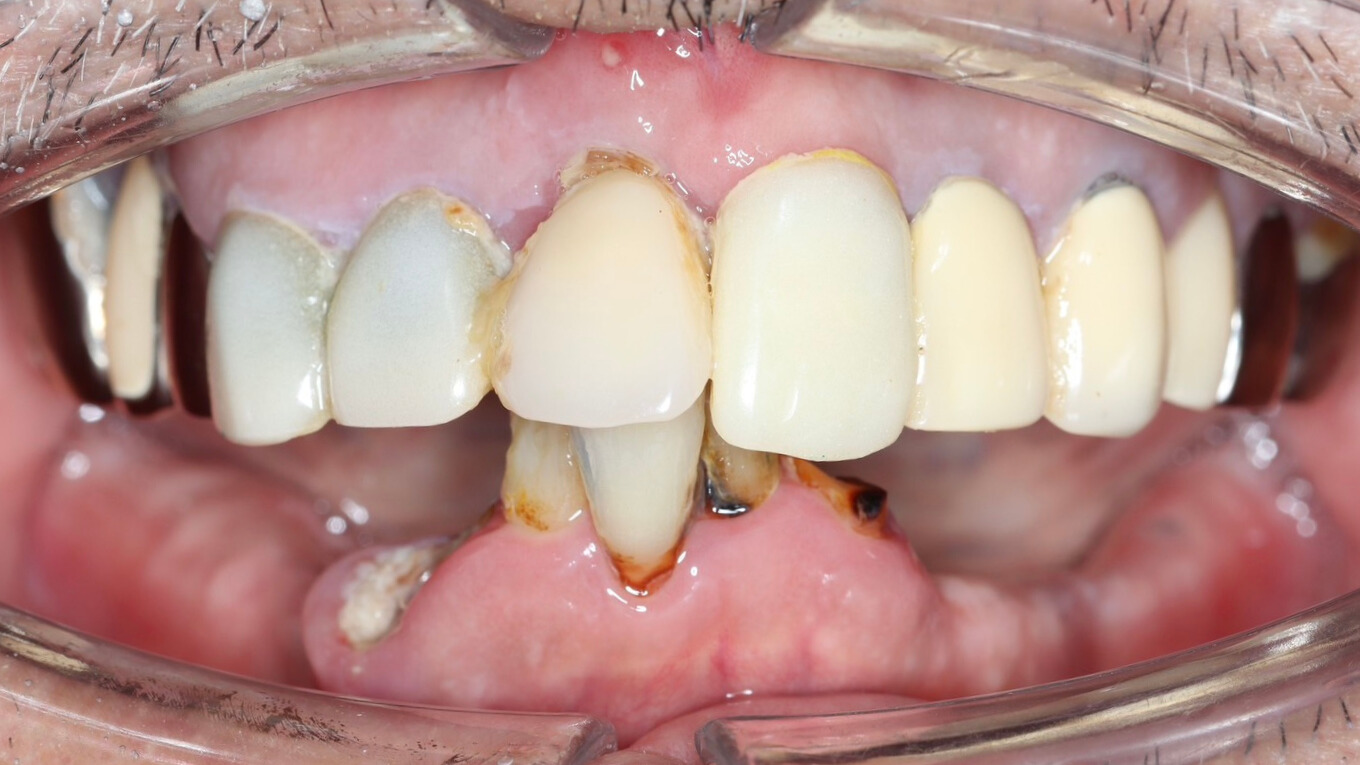

治療前

| 治療内容 | 入れ歯が嫌で、固定式の歯を希望された患者様です。 オールオン4治療を行い、下顎に4本のインプラントを埋入し、オペ当日に即日仮歯を入れました。 |